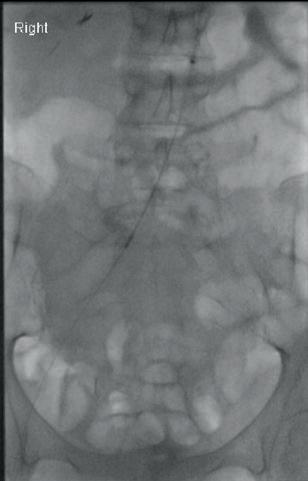

Left: Pre- and postoperative images (courtesy of Dittmar Böckler) of the first European implantation of the Gore Tag TBE; above: Dittmar Böckler performing the implantation